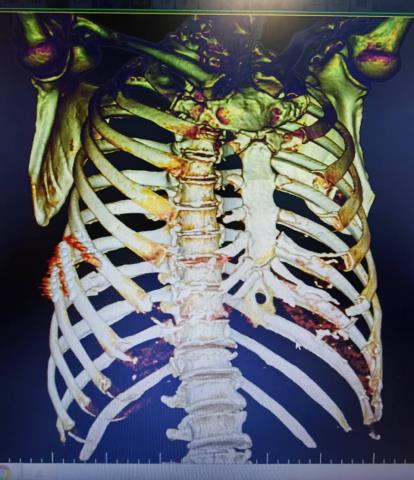

• 骨创伤治疗仪联合胸腔镜下肋骨骨折内固定手术治疗多发肋骨骨折合并血气胸的临床疗效

摘要:目的 探讨胸腔镜下肋骨骨折内固定术后,辅助给予骨创伤治疗仪,治疗多发肋骨骨折(MRF)合并血气胸的临床疗效及安全性。方法 选取2021年1月-2024年1月该院收治的MRF合并血气胸患者86例,采用随机数表法将患者分为两组,各43例。两组均接受胸腔镜下肋骨骨折内固定手术治疗,对照组于术后给予常规处理,观察组在对照组基础上,接受骨创伤治疗仪辅助治疗。观察两组患者近期和远期疗效。比较两组患者术前、术后3 d、术后7 d和术后14 d的血胸出血量和疼痛视觉模拟法(VAS)评分。比较两组患者术前和术后14 d的凝血功能指标[凝血酶原时间(PT)、活化部分凝血活酶时间(APTT)、凝血酶时间(TT)、纤维蛋白原(FIB)和D-二聚体(D-D)]。比较两组患者术后恢复情况(引流管留置时间、肿胀消退时间、住院时间和骨折愈合时间)和术后并发症发生情况。结果 观察组近期疗效总有效率为97.67%(42/43),明显高于对照组的81.40%(35/43),差异有统计学意义(P < 0.05)。观察组远期疗效总有效率为97.67%(42/43),与对照组的88.37%(38/43)比较,差异无统计学意义(P > 0.05)。术后3、7和14 d,两组患者血胸出血量明显少于术前,且观察组明显少于对照组,两组患者疼痛VAS评分明显低于术前,且观察组明显低于对照组,差异均有统计学意义(P < 0.05)。术后14 d,两组患者PT、APTT和TT明显长于术前,且观察组明显长于对照组,两组患者FIB和D-D明显低于术前,且观察组明显低于对照组,差异均有统计学意义(P < 0.05)。观察组引流管留置时间、肿胀消退时间、住院时间和骨折愈合时间明显短于对照组,差异均有统计学意义(P < 0.05)。观察组术后并发症总发生率为2.33%(1/43),与对照组的11.63%(5/43)比较,差异无统计学意义(P > 0.05)。结论 胸腔镜下肋骨骨折内固定术后辅助给予骨创伤治疗仪治疗,能有效地促进MRF合并血气胸患者胸腔积气和积液的吸收,减轻疼痛程度,改善凝血功能,加快术后机体恢复。值得临床推广应用。